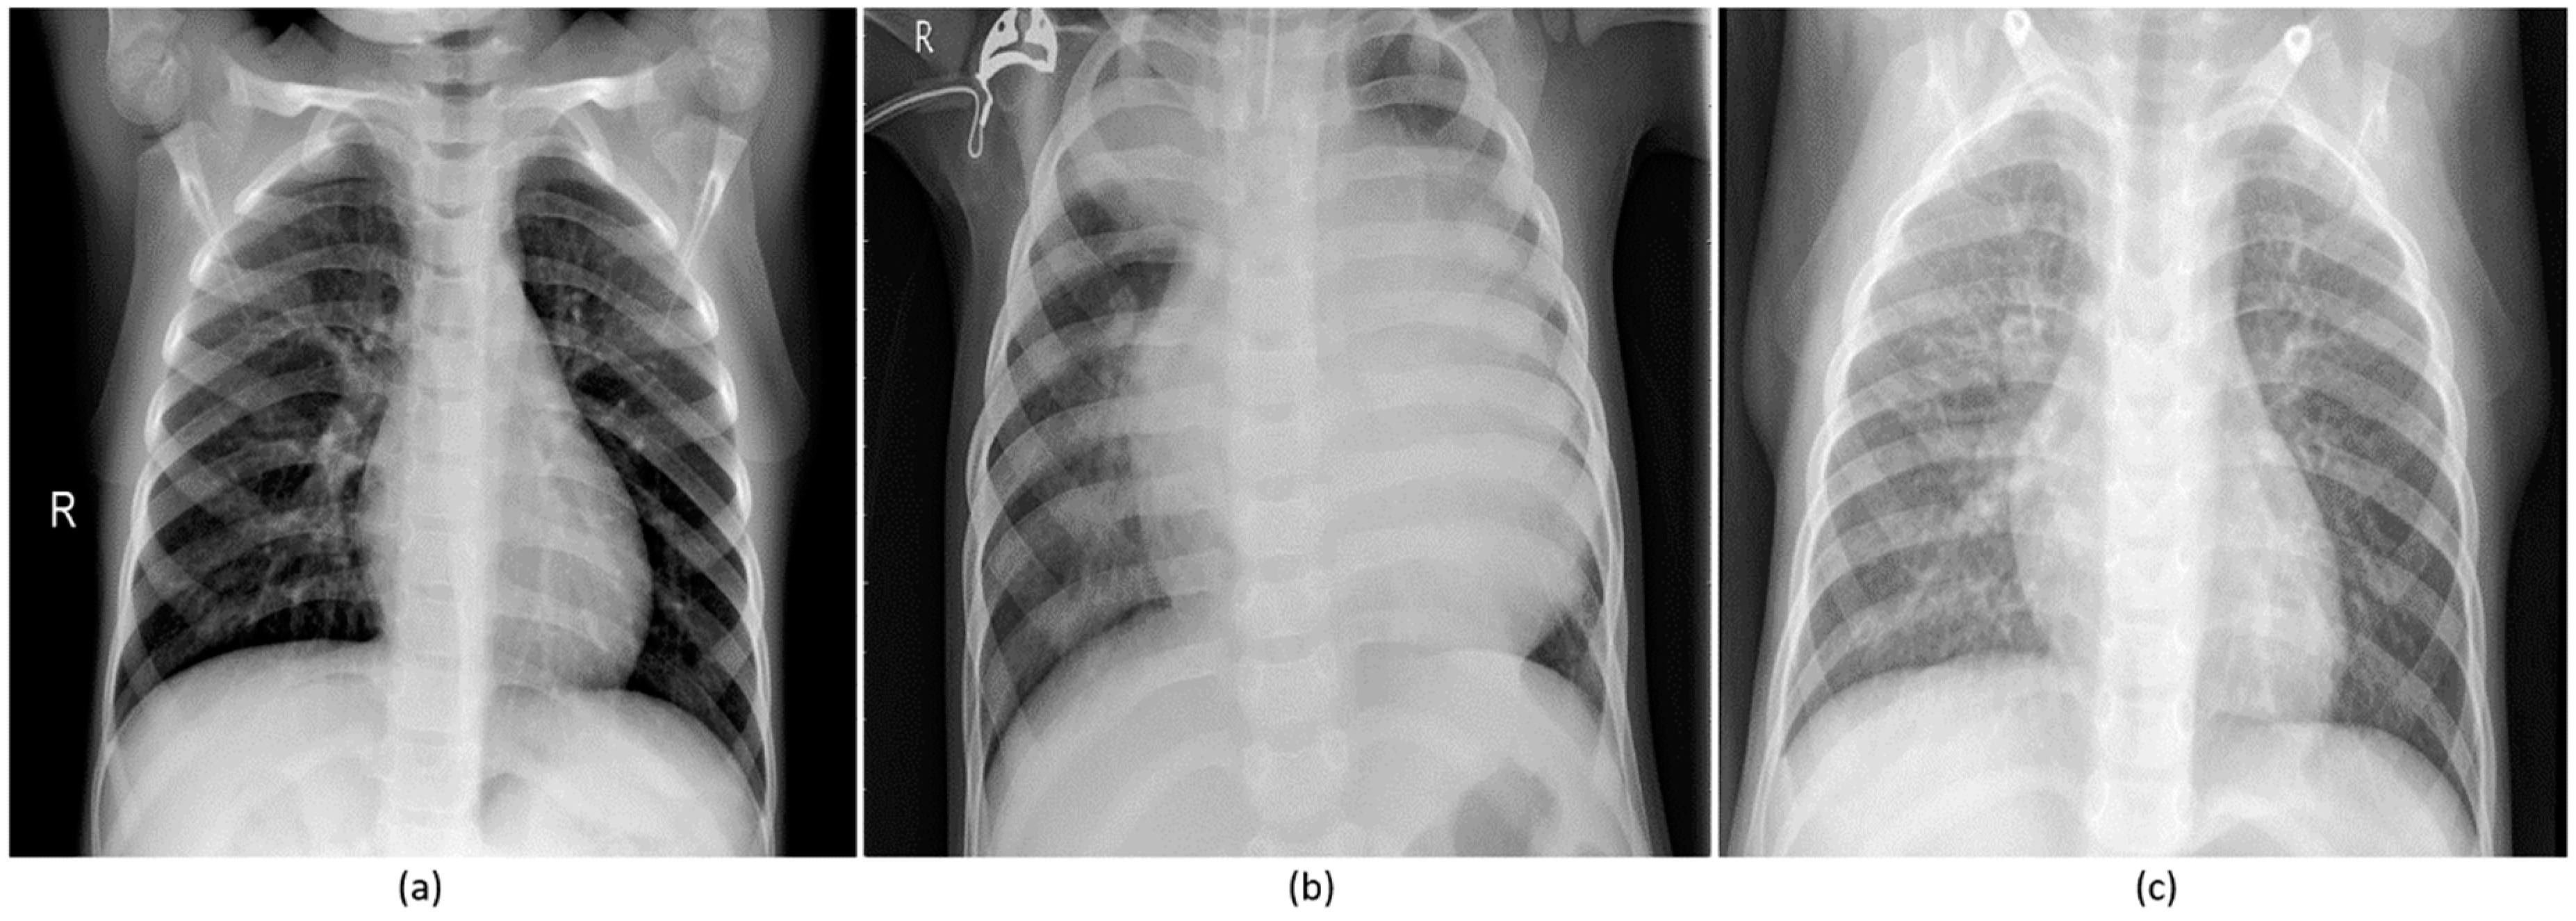

Your bronchitis rarely progresses to pneumonia. Chest X-ray showing pneumonia.

For this type of pneumonia performing a chest x-ray on the. Chest x-rays can reveal areas of opacity seen as white which represent consolidation. In complicated cases of pneumonia perform chest radiography 6 weeks after treatment to verify resolution of the pneumonia and to screen for any underlying predisposing.

This chest X-ray shows an area of lung inflammation indicating the presence of pneumonia. However chest X-ray examinations for pneumonia detection are prone to subjective variability 2 3. Please see disclaimer on my website.

It determines the pathogen that could have caused pneumonia. The differential for the radiologic finding of pulmonary consolidation includes blood pulmonary hemorrhage pus infection ie. We investigate whether chest radiographic findings could be used as predictors of severity of childhood pneumonia.

The study included 167 children aged more than 12 months. Although the chest x. A chest X-ray is often used to diagnose pneumonia.